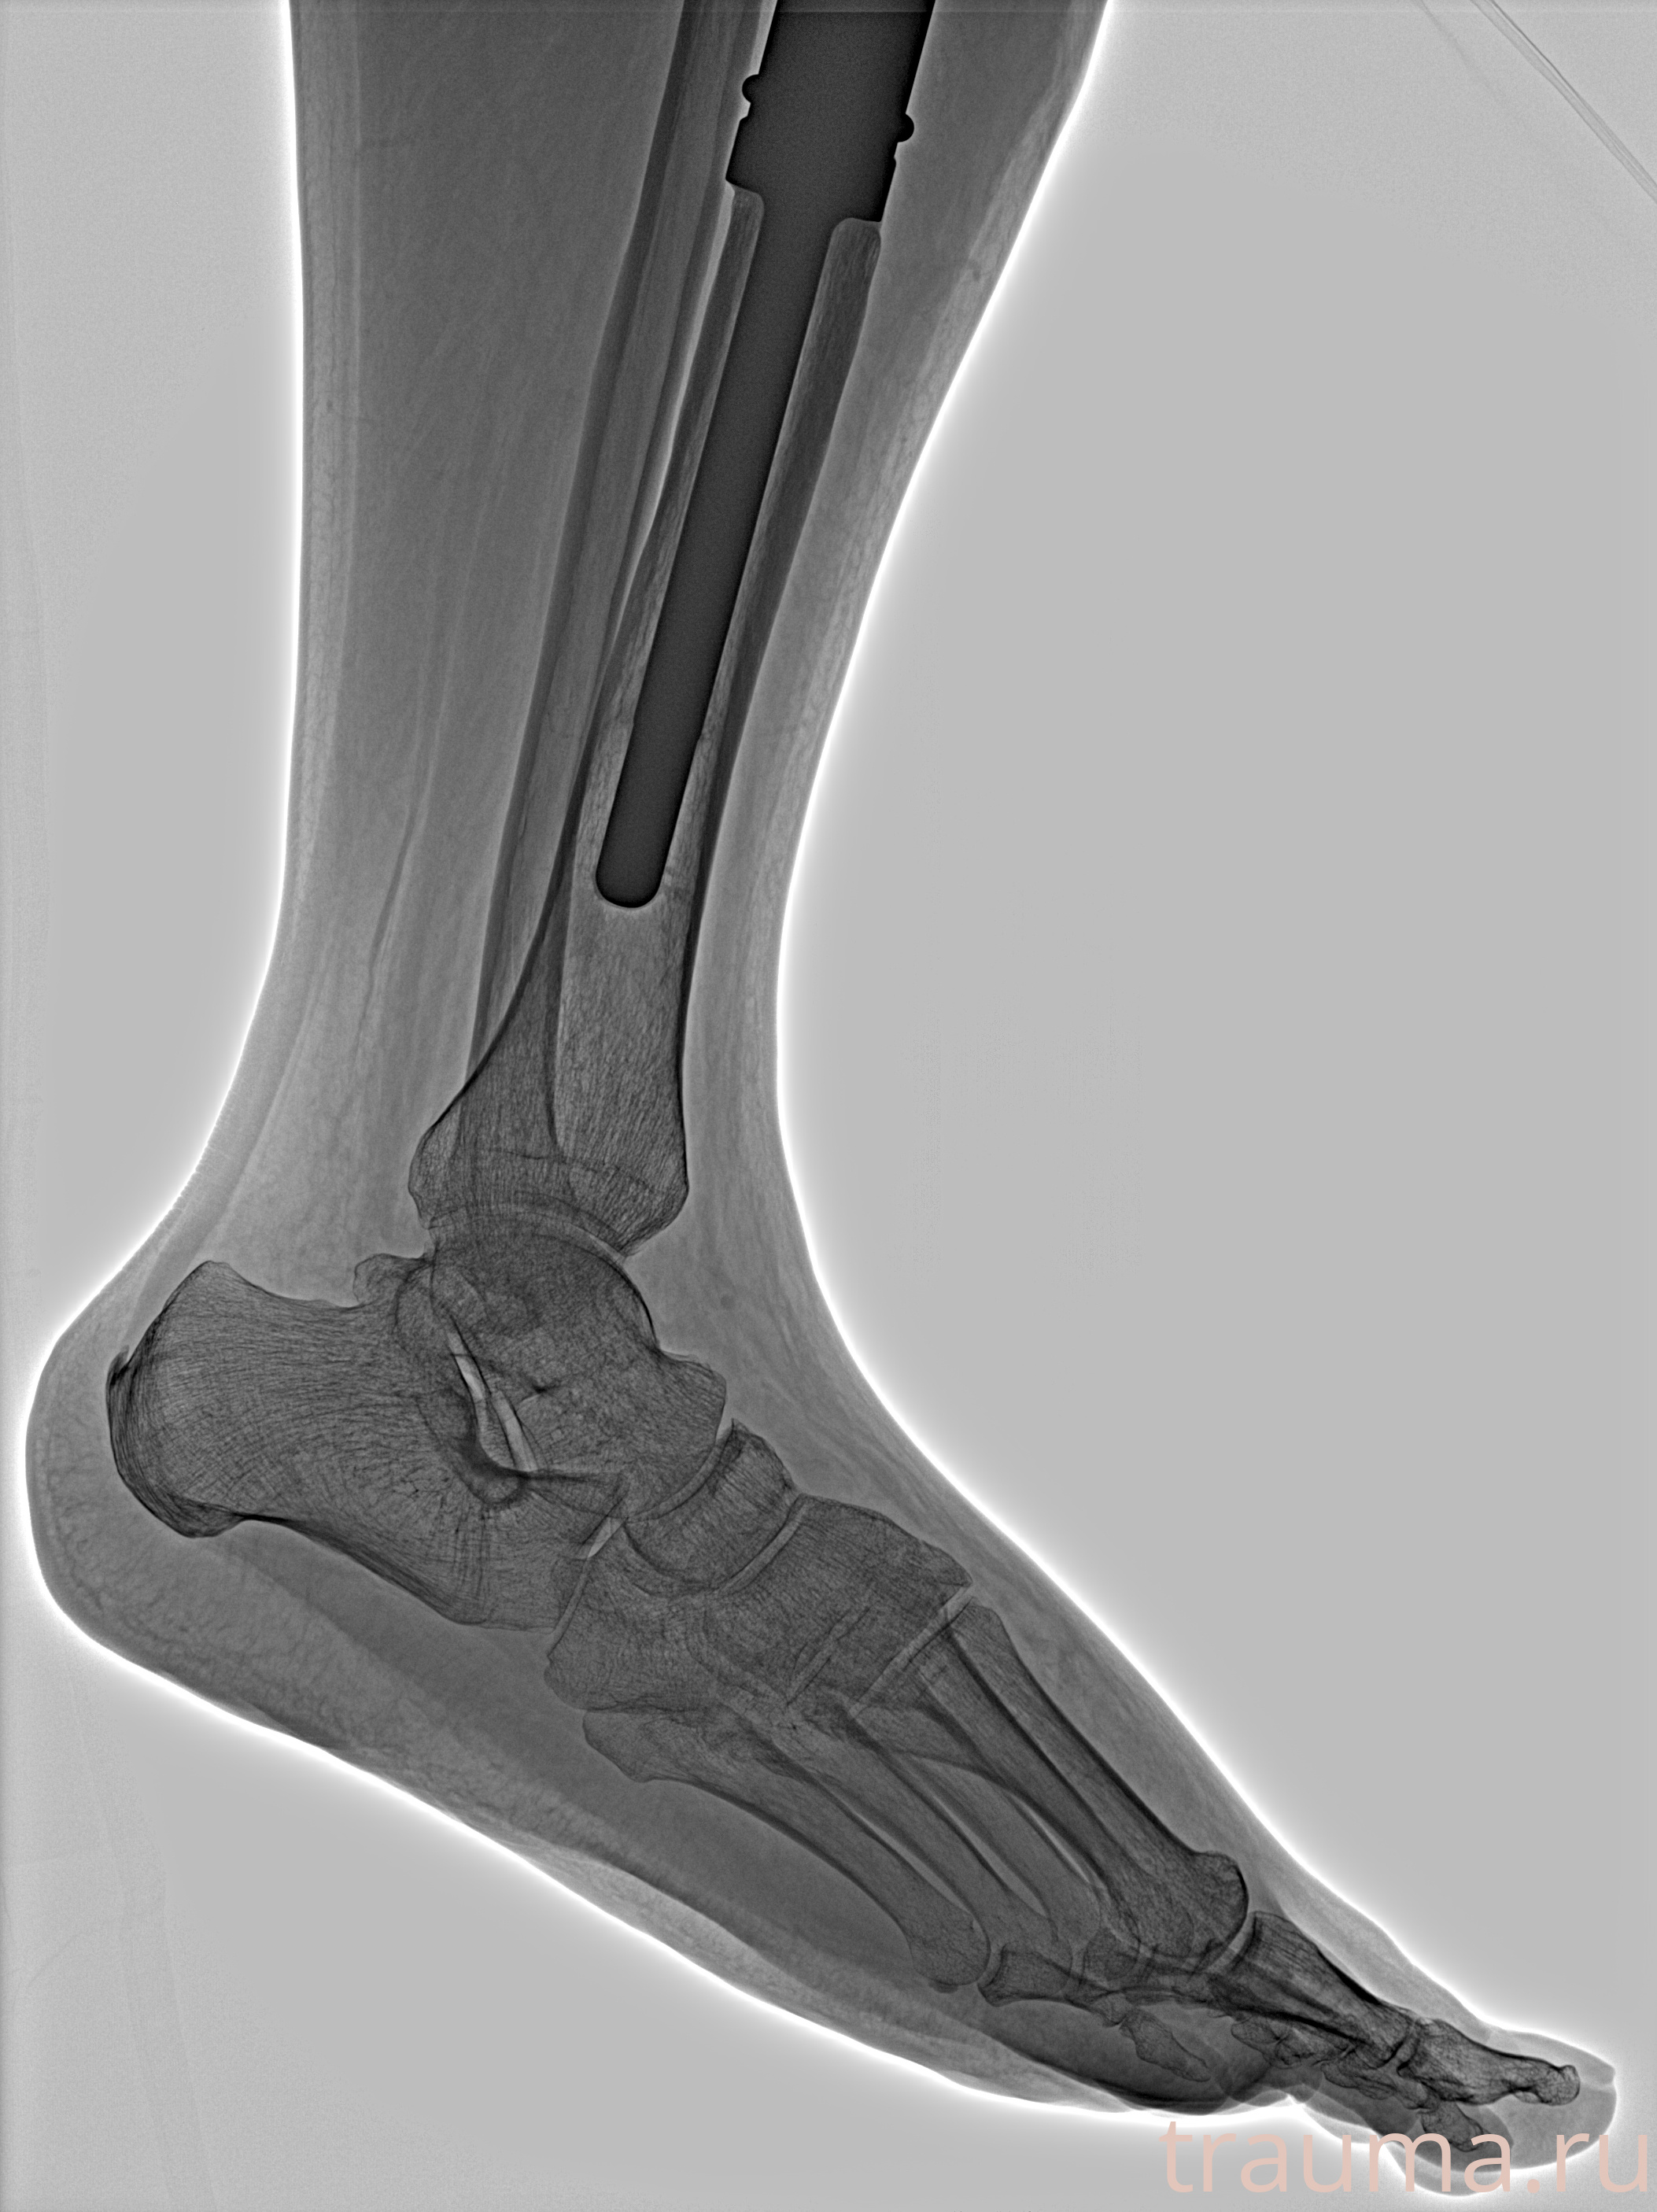

Рентген на дому: по вашему адресу приезжает врач-рентгенолог, травматолог-ортопед с мобильным рентгеновским аппаратом, проводит диагностику травмы или заболевания, делает необходимые рентгенограммы, дает рекомендации по дальнейшему лечению. Получить качественные снимки в домашних условиях возможно благодаря уникальной методике, разработанной МосРентген Центром для института  Склифосовского